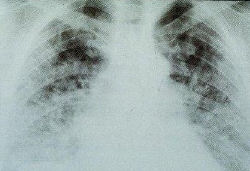

Refer to this picture for question 2. |

2. The following conditions are associated with the picture above: